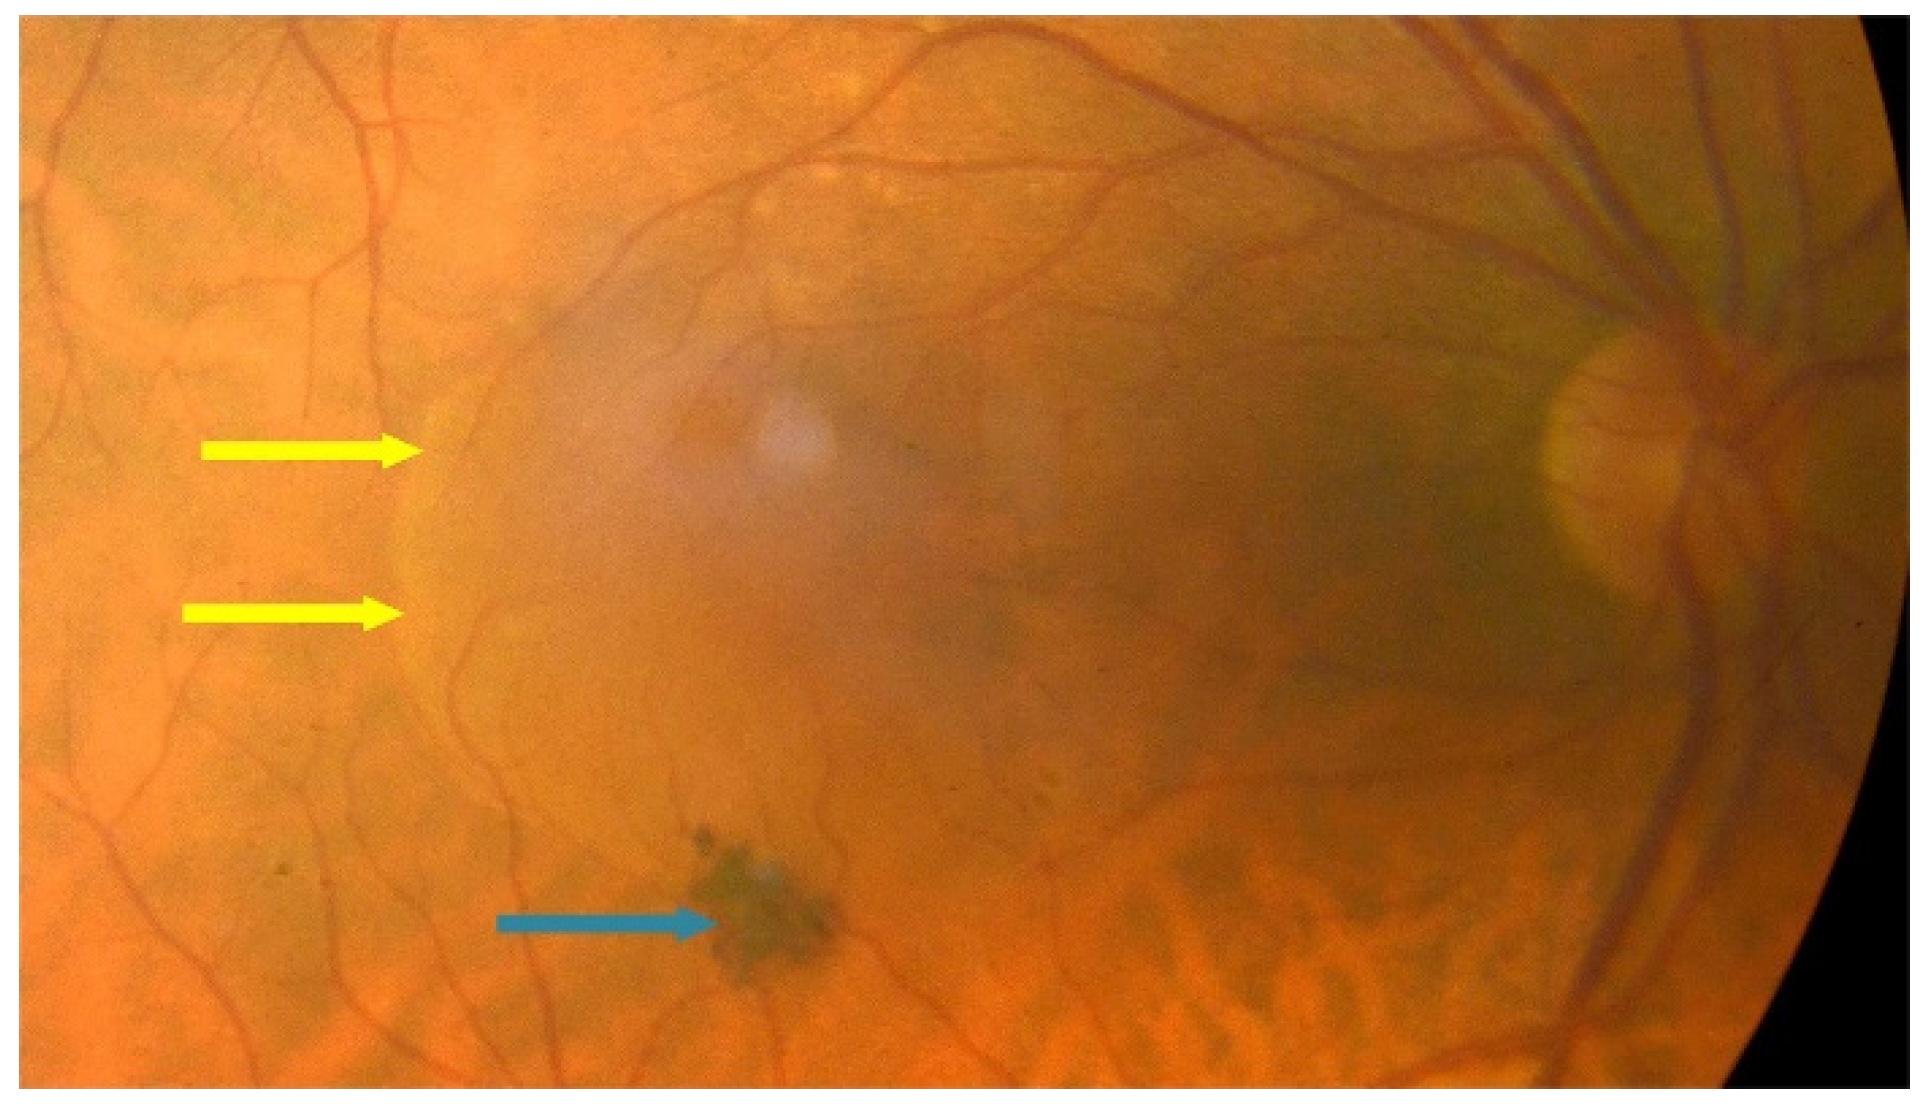

:1. Introduction

2. Treatment of Dry AMD

3. Treatment of Neovascular AMD